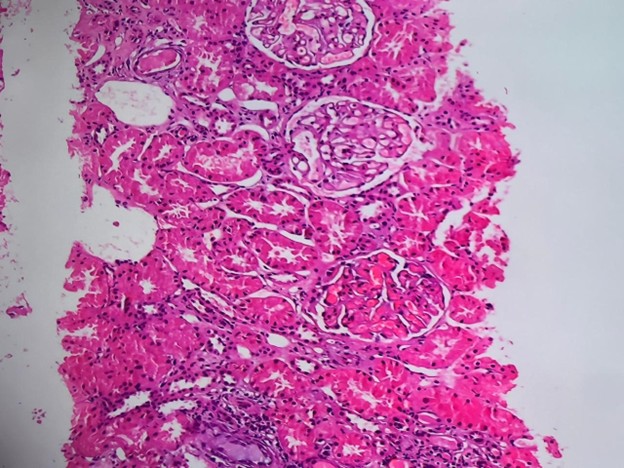

A renal biopsy was taken and sent for histopathology, which revealed Lupus Nephritis Class V (Figure 2). Immunofluorescence examination showed variable intensity full house deposits in the glomeruli; IgG deposits (+++) strongly followed by C3(++) and C1q (++) with C1q deposits also present in vessels, tubules and interstation.

Figure 2. High-power view (H&E stain) highlighting glomeruli with uniform capillary wall thickening and mild mesangial expansion, consistent with membranous features of Class V Lupus Nephritis. No significant endocapillary hypercellularity or necrosis is noted. Activity score: 03, Chronicity score: 02.